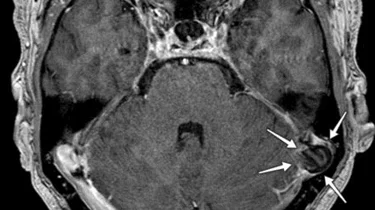

Ortopædkirurgi Lars Blønd har for nyligt udviklet en ny og vellykket operationsteknik til behandling af Artroscopisk Trokleoplastik, der udføres med en kikkertoperation.